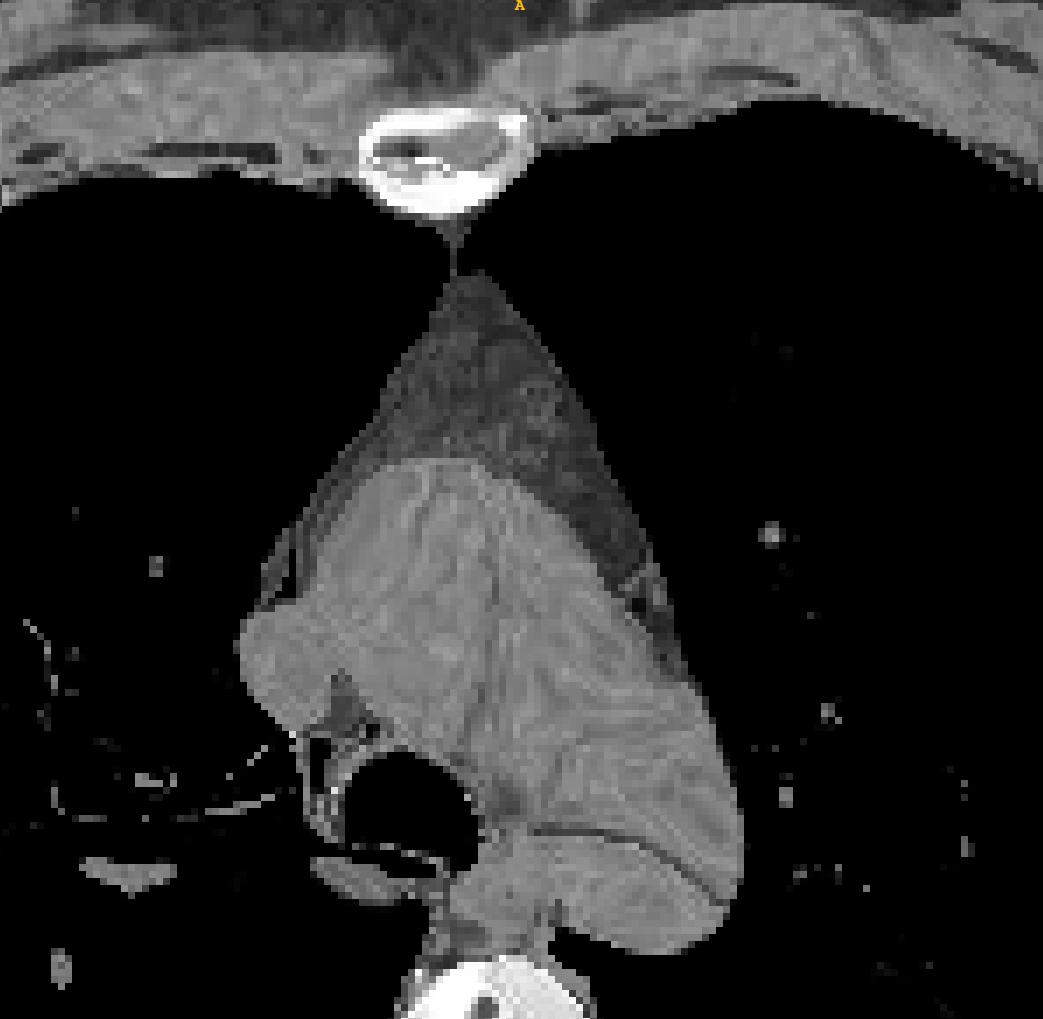

Refer to caption

Figure 2: Overview of our proposed registration model. It includes a feature extraction path(blue), a refine path(green), a pooling path(orange) and a rigid block. The number of channels C0,C1,C2,C3C_{0},C_{1},C_{2},C_{3} in the feature extraction path are 8, 16, 32, 64 respectively

As shown in Figure 2, the registration network has three paths, including a feature extraction down-sampling path, a pooling down-sampling path, and a refine up-sampling path. And the feature and pooled image are attached to the fine-tuning module in the same registration stage using skip connection.